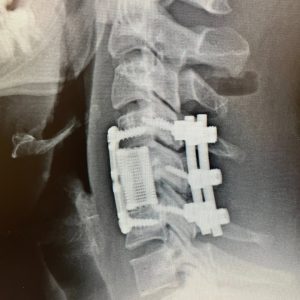

He had a fracture with the instability of his cervical spine at C5, requiring anterior and posterior surgery to decompress the nerve roots and stabilize his unstable cervical spine. He was lucky! His numbness improved, and he made a full recovery.

Too many others are paralyzed permanently from similar diving accidents. Never dive from a boat or anywhere in shallow water or water that is not absolutely safe for diving!